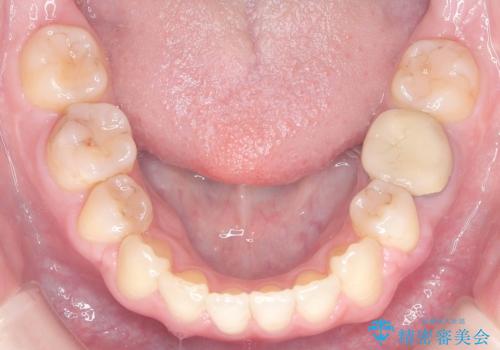

- 「歯のデコボコ、八重歯、口ボコが気になる」を主訴に来院された患者様です。

上下左右4番(4本)の歯を抜歯しワイヤー矯正で治療を行いました。

計4本の抜歯を行い、歯のデコボコと口元がすっきりし、大変ご満足していただけました。